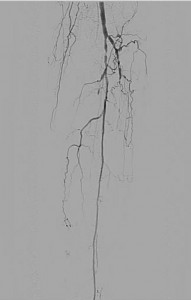

There was a severe stenosis of the left tibioperoneal trunk (Figure 2) and single vessel runoff to the foot via the left peroneal artery (Figure 3):